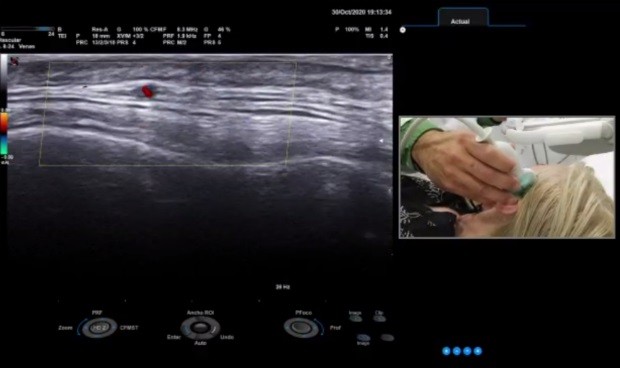

El objetivo de este taller ha sido el de aportar información clínica sobre la arteritis de céclulas gigantes y sobre el uso de la ecografía como forma de diagnóstico. “El objetivo básico de este taller es aprender el uso de la ecografía y mostrar en la práctica la posibilidad de su aplicación para el estudio de las vasculitis de gran vaso, sobre todo en la arteritis de células gigantes”, ha detallado Lluis Espadaler, jefe de servicio reumatología del Hospital Son Espases y presidente de la Sociedad balear de Reumatología quien ha destacado que gracias a ser “un proceso no invasivo” y a su “buena reproducibilidad”, “es una técnica muy apropiada para el estudio de esta patología”.

Según ha explicado Héctor Corominas, las principales novedades en este campo durante los últimos años han tenido que ver con la mejora de los ecógrafos, el mayor acceso a tecnología de última generación, disponer de mejores sondas para explorar y un mejor conocimiento de esta enfermedad, su comportamiento, sus variantes clínicas y su tratamiento. “El médico que examina a un paciente y establece una sospecha diagnóstica de arteritis de células gigantes puede realizarle una ecografía de arteria temporal, axilar o ramas aórticas a pie de cama, lo que evita desplazamientos innecesarios y segundas visitas. Se puede decidir casi de inmediato el tratamiento, evitando complicaciones graves”, ha añadido.